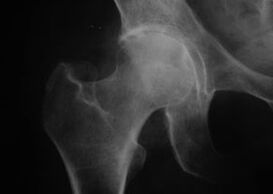

Coxatrosis, arthrosis of the hip joint

With this disease, a classic clinical picture of arthrosis is observed.

The first symptom of coxarthrosis is discomfort in the hip joint after physical activity.

With progressive coxarthrosis, increased pain, stiffness and limited mobility appear.

Patients suffering from a severe form of coxarthrosis spare the affected limb, avoiding stepping on it and, when stationary, choose positions in which the pain is minimal.